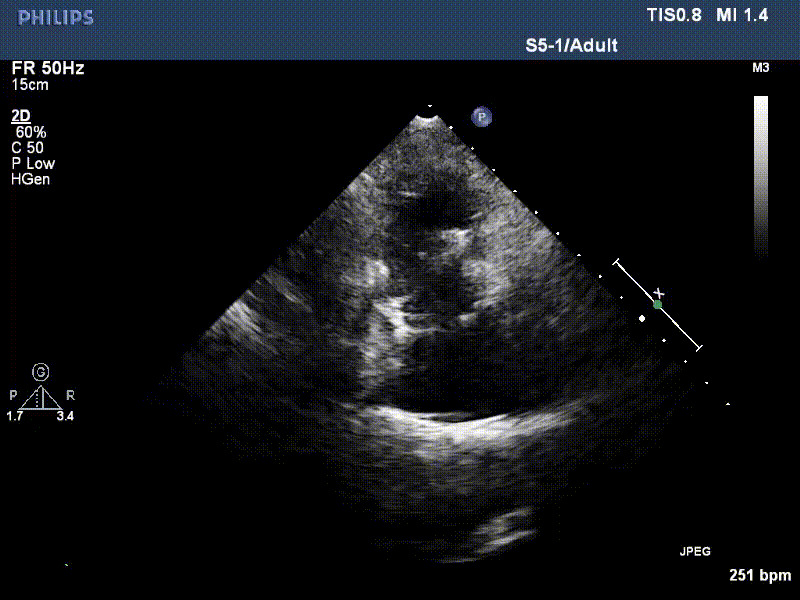

流并分別伴有房顫和房撲,高外科手術風險。術前超聲提示,兩例患者下腔靜脈寬度分別為13mm和29mm,右房內(nèi)徑(上下徑和左右徑)分別為52×41mm和53×43mm,彩色多普勒顯示極重度三尖瓣反流,VCW分別為14×15mm和10mm。

1年前,兩例患者因難治性雙下肢水腫輾轉(zhuǎn)多家醫(yī)院尋求救治,考慮到兩例患者高齡、基礎疾病多、STS評分高,不適合傳統(tǒng)外科開胸手術,葛均波院士及其團隊周達新教授、潘文志教授、張源博士、陳莎莎博士、陳丹丹博士聯(lián)合心外科王春生、魏來主任,麻醉科繆長虹、郭克芳主任以及心超室的潘翠珍教授、李偉教授共同討論決定,采用我國創(chuàng)新器械LuX-Valve Plus經(jīng)血管三尖瓣置換系統(tǒng)為患者進行手術。相較于第一代產(chǎn)品LuX-Valve,LuX-Valve Plus經(jīng)血管三尖瓣置換系統(tǒng)對輸送系統(tǒng)進行了全面升級,實現(xiàn)了經(jīng)頸靜脈入路的方式,進一步減小了手術風險和對患者的創(chuàng)傷。目前隨訪1年心超結(jié)果顯示,三尖瓣極重度反流消失,人工三尖瓣瓣膜穩(wěn)定牢固,瓣葉活動度良好,右心室及下腔靜脈明顯縮小,心輸出量增加。兩位老人手術后沒有出現(xiàn)過胸悶氣促的癥狀,下肢水腫緩解,活動耐力提升,生活質(zhì)量也大為提高。

圖2 患者植入LuX-Valve Plus后,1年隨訪心超提示無三尖瓣反流